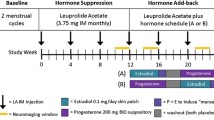

When BSO and BSO+ERT groups were separately compared to AMC and SM, there was a significant effect of group on performance (F(3,67)=3.55, p=0.02, partial η2=0.14; Fig. 2). The only significant group difference in task performance revealed by post hoc comparisons was between AMC and SM groups: AMC had significantly better performance than SM (t(67)=3.12, p=0.01, Tukey’s HSD test). There were no other significant group differences revealed by post hoc comparisons. Thus, BSO did not negatively influence memory performance, although past literature would have suggested that women with BSO and SM would have reduced performance relative to BSO+ERT and AMC.

Women with bilateral salpingo-oophorectomy who were not taking hormone therapy (BSO) and those who were taking 17β-estradiol-based hormone therapy (BSO+ERT) were not significantly different from each other or AMC and SM; error bars represent standard error of the mean; *=p<0.05

When BSO (Combined) was compared to AMC and SM, there were no significant group differences in average activation for any of the ROIs. However, when BSO and BSO+ERT groups were separated and compared to AMC and SM, there was a significant effect of group on average activation in the right posterior lateral hippocampus (F(3,65)=4.07, p=0.010, partial η2=0.15); both BSO (t(65)= −2.84, p=0.03, Tukey’s HSD test) and SM (t(65)=3.20, p=0.01, Tukey’s HSD test) had significantly lower activation than BSO+ERT (Fig. 3). None of the other groups differed significantly in right posterior lateral hippocampus activation according to post hoc contrasts. Given a large effect size of Cohen’s f=0.42, a significance threshold of 0.05, 72 participants, and two covariates (scanner site and history of cancer treatment), we determined power for this analysis to be sufficient (power=0.84).

Effect of group on right posterior lateral hippocampal region-of-interest activity; Women with bilateral salpingo-oophorectomy who were not taking hormone therapy (BSO) and women in spontaneous menopause (SM) showed lower activation (mean parameter estimate: PE) than women with BSO who were taking 17β-estradiol-based hormone therapy (BSO+ERT) during Novel compared to Repeat face-name pair encoding; age-matched premenopausal control women (AMC) did not contribute to significant group differences; error bars represent standard error of the mean; *=p<0.05